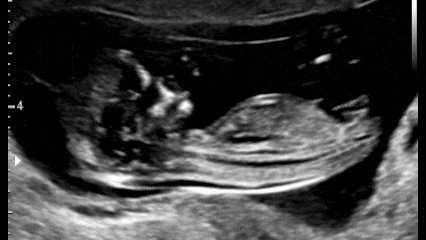

对,你没听错,就是要宝宝们(不是宝妈)躺平!躺平!躺平!不能侧躺、坐着、趴着,也不能低头,更不要伸懒腰……当然最好还不要乱动(超声医生们超爱的标准NT躺)。

标准NT躺

NT,英文Nuchal Translucency,即颈项透明层(蓝色区域)。NT超声检查是孕早期一项重要的超声筛查项目,主要用于评估胎儿染色体染色体异常(如唐氏综合征)或其他严重结构畸形的风险程度。

NT检查时间有严格规定

孕11周~13周+6天时进行

(即胎儿头臀长45~84mm)